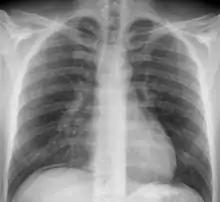

Радіогра́фія (англ. radiography; нім. Radiographie f) — галузь радіології, яка займається використанням радіації[джерело?] (зокрема рентгенівських променів) для отримання зображень на фотоплівці або флуоресцентному екрані (радіоскопія). Рентгенівські промені по різному проходять крізь речовину залежно від її природи, густини й товщини. Промені можуть залишати сліди на фотоплівці, у результаті чого виходить рентгенівський знімок. Це явище широко застосовується в медицині для вивчення кісток і тканин і в промисловості для контролю, наприклад, за звареними швами трубопроводів.

Радіографія в медицині має ширше значення, проте, найвідомішими радіографічними методами є:

- Рентгенографія — метод діагностики стану кісток та тканин організму (можливо з контрастуванням) застосовуючи рентгенологічне випромінювання.